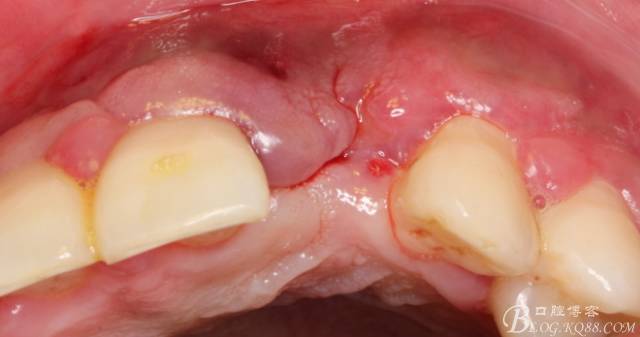

于是我果斷告知患者,手術(shù)失敗了,不能拖延,如不及時(shí)處理,炎癥繼續(xù)發(fā)展會(huì)很快波及鄰牙牙槽骨?;颊呓邮芪业慕ㄗh。切開(kāi)翻瓣,骨粉及生物膜消失了,骨吸收嚴(yán)重,幸運(yùn)的是,因?yàn)樘幚砑皶r(shí),鄰牙骨支持依然存在。